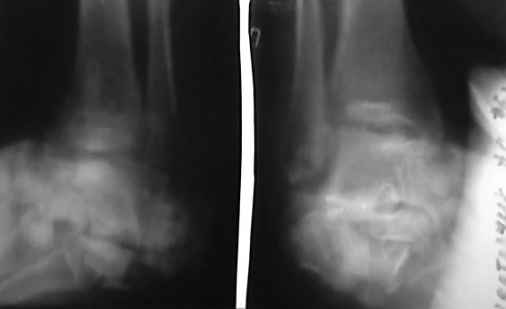

Здравствуйте,коллеги!Все оказалось даже хуже!Сегодня больной госпитализирован и:

С левой стопой дело похуже. Нужен прямой снимок, да и боковой не помешает повторить на всю стопу, ну и плюс аксиальный. Готовтье аппарат.

Отправляю снимки(свежие)и фото стоп.

С уважениемД.Б.